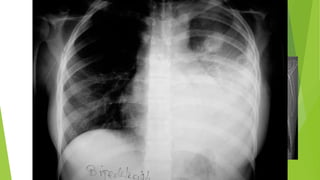

Signo del Broncograma Aéreo:

 Edema agudo de pulmón

 Infarto Pulmonar

Signo del BroncogramaAéreo:  Edema agudo de pulmón

Signo del BroncogramaAéreo:  Infarto Pulmonar